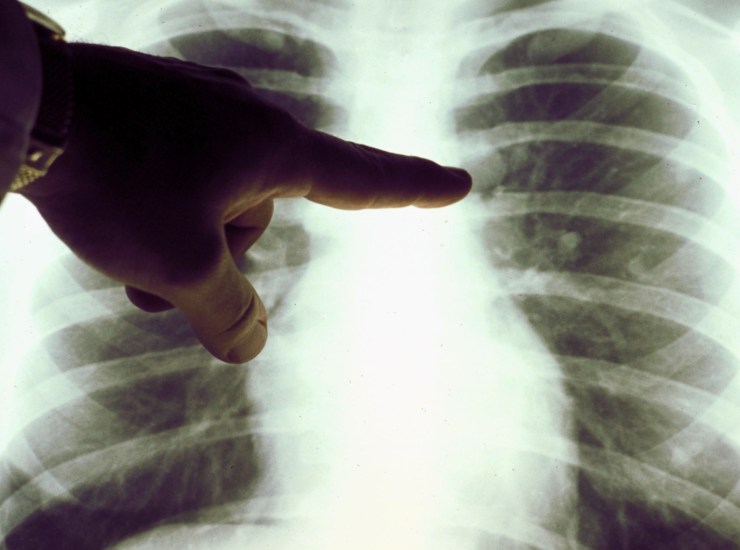

Tumore polmonare, nuovo farmaco riduce dell’80% rischio morte o recidiva. Nei pazienti che presentano stadio precoce e positivi a mutazione genica

Un nuovo farmaco, Osimertinib, ha mostrato di ridurre dell’80% il rischio di morte o recidiva per tumore ai polmoni in pazienti con cancro polmonare non di piccole cellule il cui stadio è precoce e con mutazione del fatto EGFR dopo operazione chirurgica. Lo conferma uno studio Adaura fase III eseguito su 682 pazienti. I medici hanno presentato i suddetti dati al congresso dell’Asco.

Dopo 2 anni da quando è cominciato il trattamento, circa l’89% dei pazienti curati con Osimertinib ha superato la malattia rispetto ai pazienti curati con placebo, pari al 53%. Secondo il direttore Divisione di Oncologia Toracica all’Istituto Europeo di Oncologia (IEO) di Milano Filippo De Marinis, la suddetta riduzione di rischio morte o recidiva dell’80% ” in un setting di pazienti in stadio precoce e quindi potenzialmente curativo è sicuramente un dato senza precedenti che porterà a un cambio della pratica clinica. Si tratta di risultati che vedranno inevitabilmente l’affermarsi delle terapie target e, in particolar modo, dell’inibitore di EGFR osimertinib, come terapia standard per questi pazienti“.